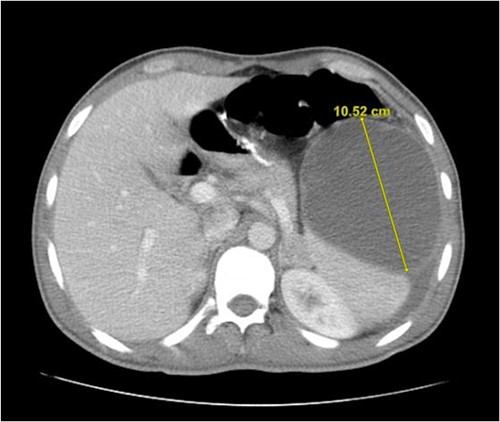

The patient is a 26-year-old male with no chronic medical illnesses who underwent LSG 1 year before his presentation. He presented to the emergency department complaining of intermittent abdominal pain for 4 days. The patient reported feeling fullness in the left upper quadrant area and denied any recent history of abdominal trauma. Examination revealed a swelling at the left upper quadrant. Laboratory investigations were unremarkable. Contrast-enhanced computed tomography showed a large septated cystic lesion of 10 cm compressing the left kidney (Fig. 1). A magnetic resonance image confirmed a non-enhancing cyst with internal septations (Fig. 2). Several factors made us offer laparoscopic exploration and cyst removal to the patient, including the reported symptoms, the cyst size and to confirm the nature of the cyst.

An abdominal contrast-enhanced computed tomography showing a cyst originating from spleen